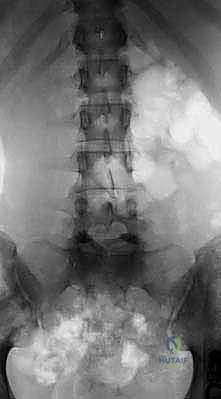

- الأشعة السينية الديناميكية (Dynamic X-rays): صور في وضعية الانحناء للأمام والخلف لتقييم مدى عدم استقرار الفقرات وحركتها غير الطبيعية.

في حالات الانزلاق الفقاري من الدرجة الأولى أو الثانية، قد يكون العلاج التحفظي (العلاج الطبيعي، الأدوية، الحقن الموضعي) فعالاً. ولكن، عندما نتحدث عن الانزلاق عالي الدرجة (الثالثة فما فوق)، ومع وجود أعراض عصبية واضحة، يصبح التدخل الجراحي هو الخيار الطبي الوحيد الفعال لمنع تدهور الحالة العصبية وإصلاح التشوه الميكانيكي.

1. تحرير الأعصاب المضغوطة (Decompression).

2. إعادة الفقرات إلى وضعها التشريحي الأقرب للطبيعي بقدر الإمكان.

3. تثبيت ودمج الفقرات لمنع الانزلاق المستقبلي (Fusion).